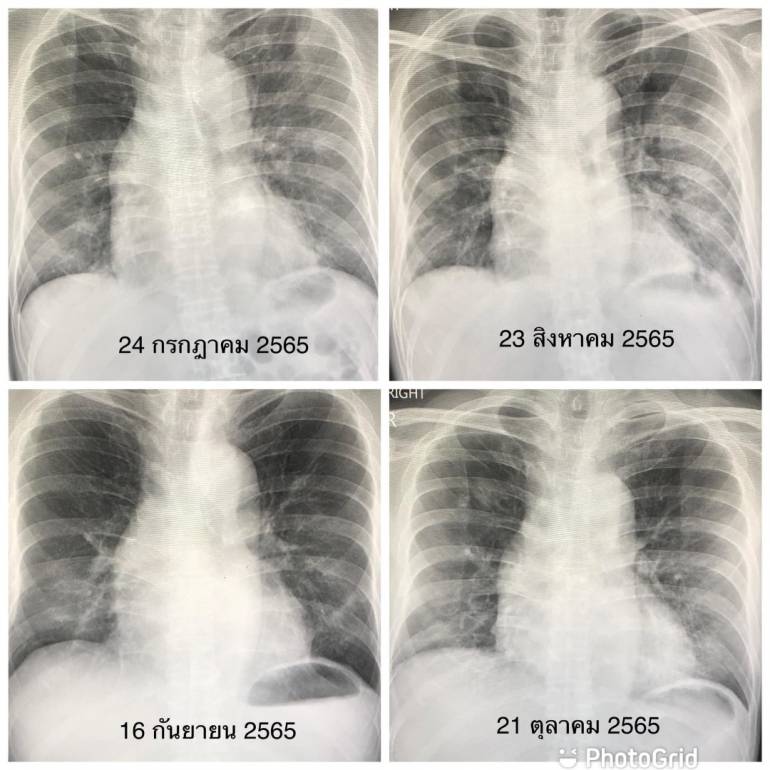

แพทย์ยกเคส หายมะเร็ง แต่พบ “ปอดอักเสบจากโควิด” 4 ครั้ง | Thai PBS News … 15 ภาพเอกซเรย์ร่างกายของมนุษย์ ที่แสดงให้เห็นความอัศจรรย์ของร่างกายเรา …

หมอมนูญ เผยภาพ เอกซเรย์ปอดผู้ป่วยโควิด ระลอกใหม่ ชี้ รอบนี้รุนแรงกว่าเดิม Facebook

ภาพต่อภาพ เทียบเอกซเรย์ชัดๆ ปอดผู้ป่วยโควิด “สาหัส” กว่าคนสูบบุหรี่จัด … ปักพินในบอร์ด เป๋าโดนๆ

เปิดภาพเอกซเรย์ก่อน-หลังปอดผู้ป่วยโควิด หลังได้รับพลาสมาขอบคุณที่ต้องการเสริมสร้างความรู้ด้วยการอ่านบทความ